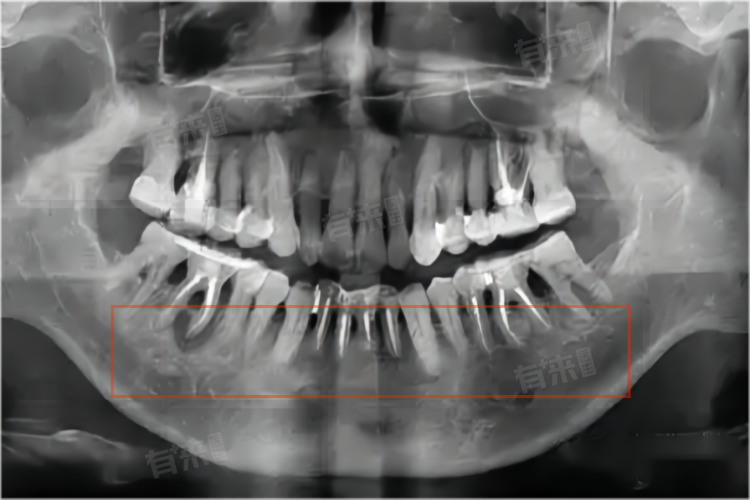

- 对于牙槽骨薄的患者,正畸治疗过程中需要特别注意牙齿移动的方式。例如避免进行大范围的牙齿移动或快速矫治,尽量采用平动或小范围的倾斜移动,以减少对牙槽骨的压力。同时医生会密切监测牙槽骨的变化,定期拍摄X线片评估牙槽骨的情况。

- 在正畸治疗前,医生会通过CBCT(锥形束CT)等影像学检查,精确测量牙槽骨的厚度和高度,评估牙齿移动的可行性。如果牙槽骨过于薄弱,牙齿移动可能会导致牙槽骨穿孔或牙齿松动,这种情况下可能需要先进行牙槽骨增量手术,如引导骨组织再生术,增加牙槽骨的厚度后再进行正畸治疗。